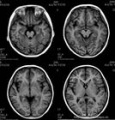

烟雾病